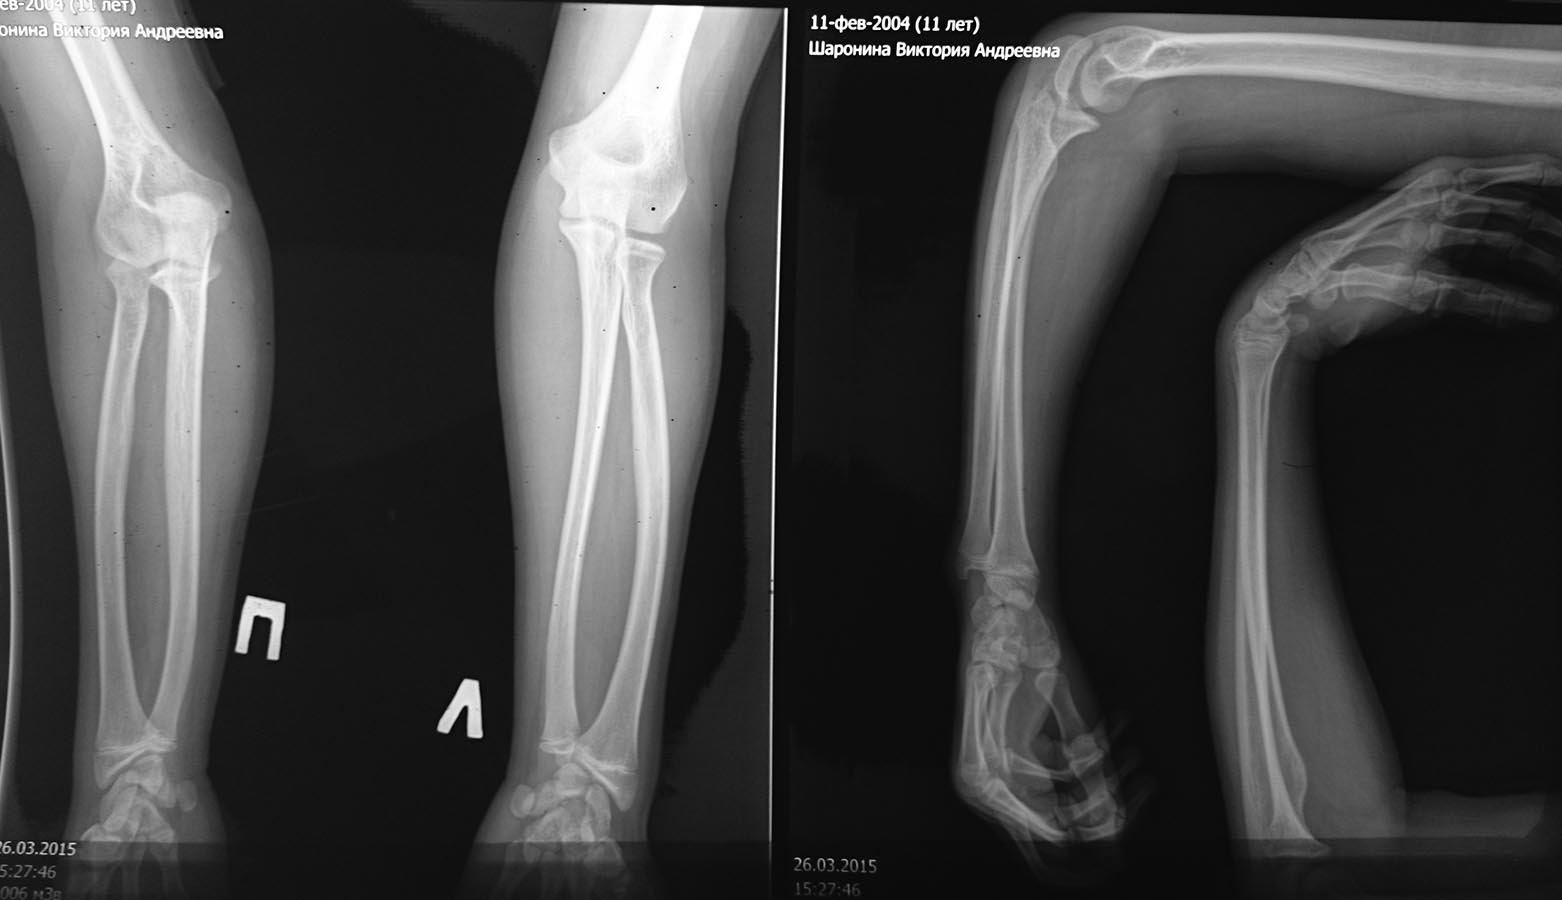

Re: Застарелый вывих головки луча и парез лучевого нерва у подростка.

Ригидности нет. Пассивные движения пальцев и кисти не ограничены. Пациент учится в школе,этой рукой хорошо пишет,пользуется ложкой,ребенок-хорошая адаптация.

Для сравнения-рентген здоровой конечности